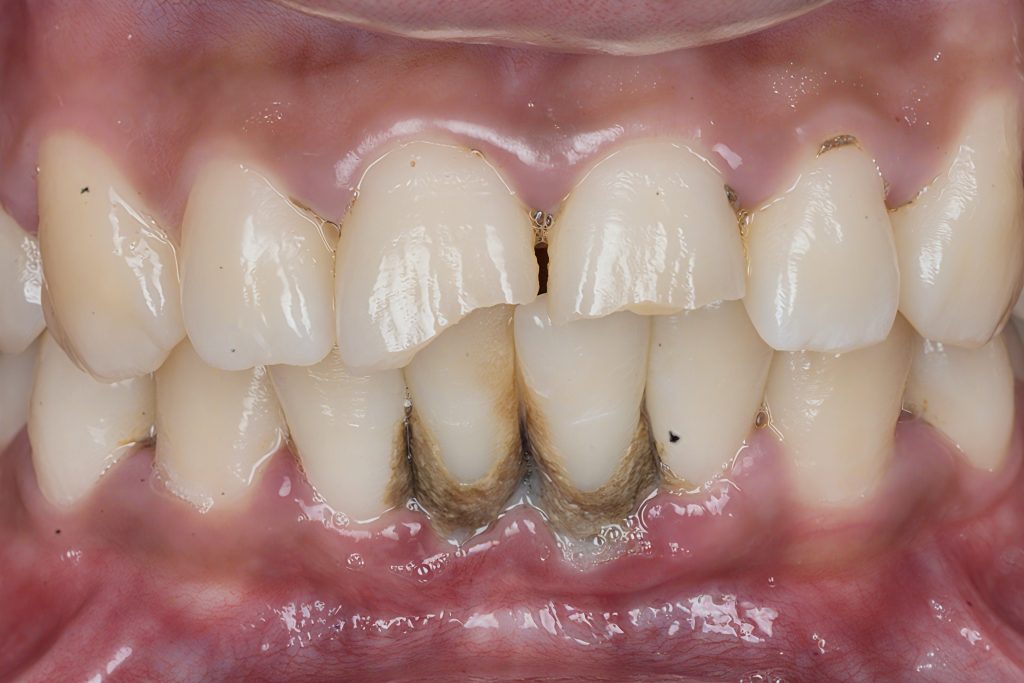

1. Pre-Operative Assessment

High-resolution photography showed incisal wear, fractures and composite delamination. Shade mapping was carried out under cross-polarised dental photography to identify enamel, dentin, and halo zones.